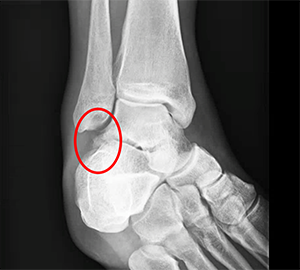

X-ray image demonstrating a lateral process fracture. Notice that thefracture is difficult to identify leading many of these injuries to be initially missed